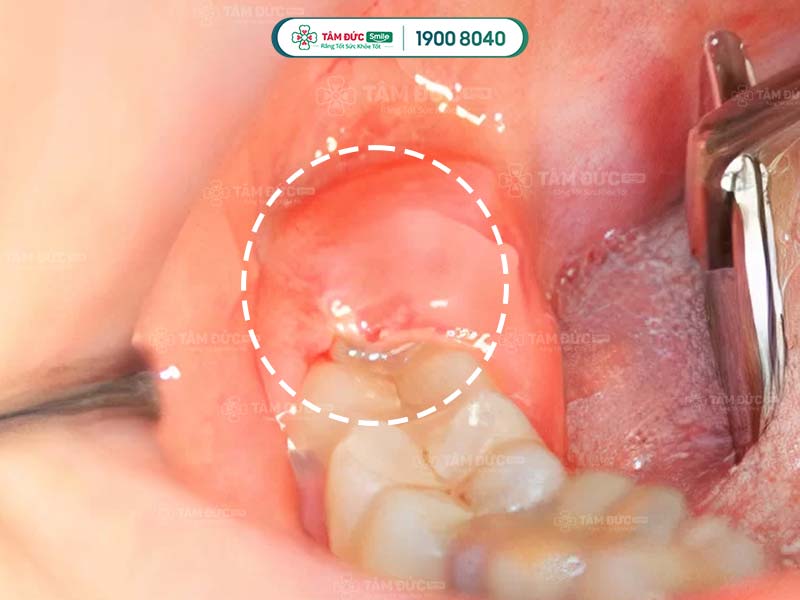

1.3. Đau do chấn thương mô mềm

Khi nhổ răng khôn, vùng má, vòm miệng, nướu, hàm…là những mô mềm rất dễ bị tổn thương. Nếu Quý khách bị chấn thương mô mềm, tình trạng đau nhức có thể kéo dài tới vài tuần. Những cơn đau dai dẳng, âm ỉ tạo cảm giác khó chịu, ảnh hưởng nghiêm trọng tới sức khỏe.

Chấn thương mô mềm có thể gây đau đớn kéo dài